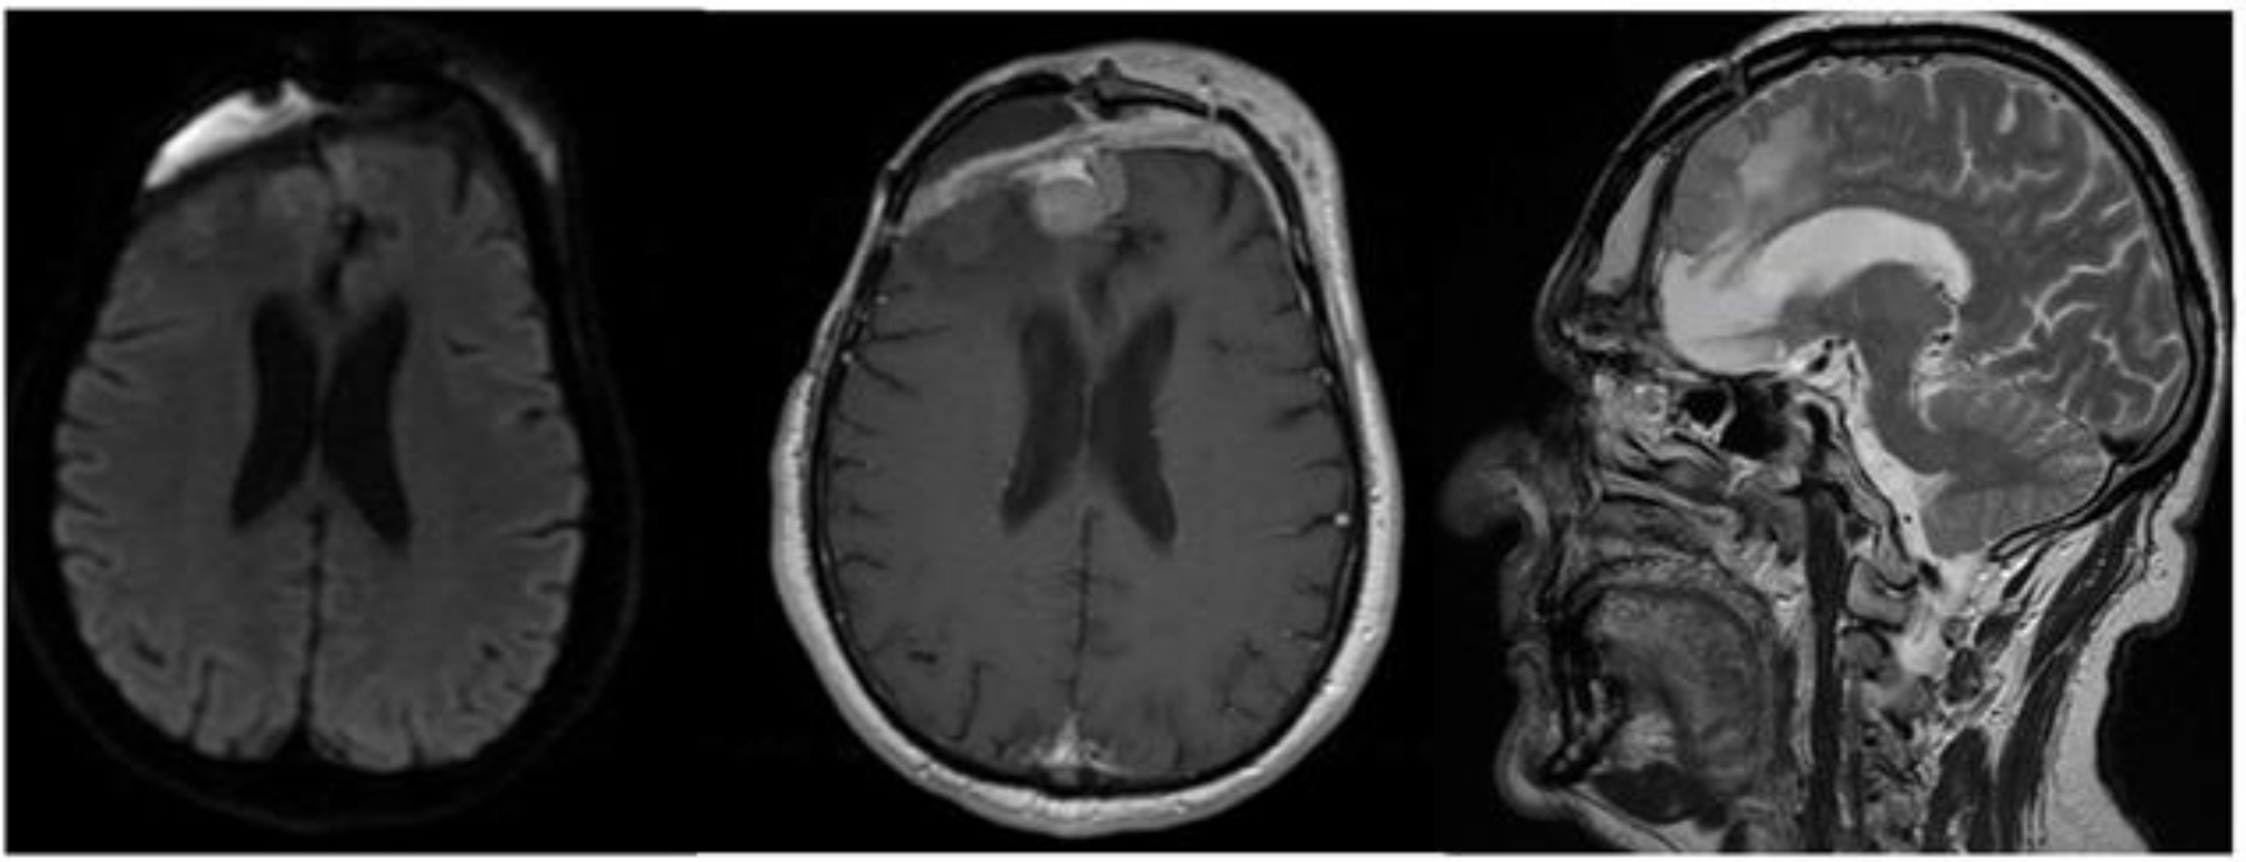

The CT scan showed removal of tumor and empyema and the appearance of pneumocephalus (Figure 5). A few days later and after antibiotic therapy, we performed a combined right frontal craniotomic and transsphenoidal endoscopic rescue procedure with fascia lata to seal off the cranial base from nose cavity. The post-operative CT scan showed the persistence of pneumocephalus with mass effect. Six days later, we performed a new intervention in collaboration with plastic surgeons: a chimeric perforator anterolateral thigh (ALT) free flap including a superficial monitor skin paddle and a portion of rectus femoris muscle was used to close the spheno-ethmoidalis defect (Figure 6 and Figure 7). The post-operative MRI showed the resolution of the pneumocephalus, and the patient was discharged with no neurological symptoms.

Figure 6.

Post-operative brain MRI after evacuation of the epidural empyema, cranial bone flap removal and reconstruction by means of anterolateral thigh flap.